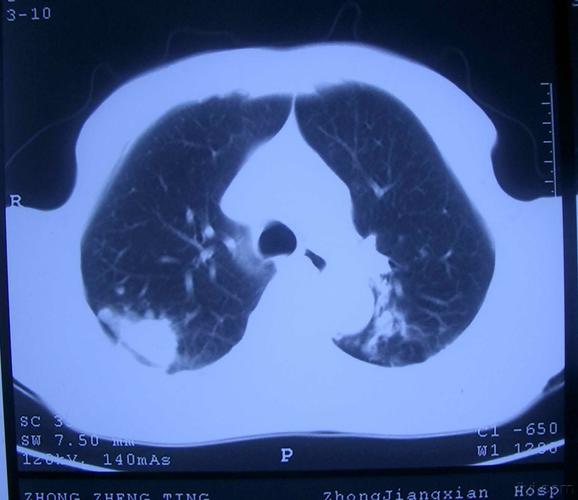

肺部有阴影,肺部有阴影是什么原因

又一个病例讨论-咳嗽,黄痰,肺部阴影

肺部出现阴影可能预示多种疾病

肺部有阴影CT

肺部阴影诊断

新冠肺部阴影

肺部阴影图片

肺部阴影有几种可能

肺部阴影图片胸片